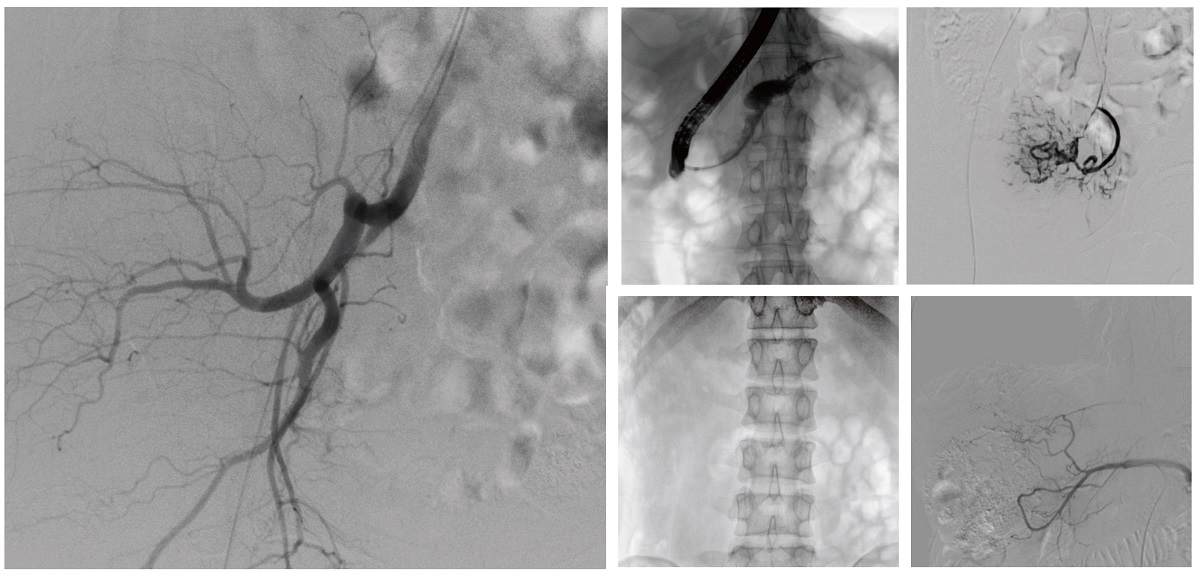

醫(yī)院引進(jìn)的普愛醫(yī)療移動式平板介入中C,其高清成像能力覆蓋骨科、介入科、泌尿外科、婦產(chǎn)科等多科室,能夠滿足介入微創(chuàng)手術(shù)的多樣化需求。

設(shè)備的移動式設(shè)計,無需對現(xiàn)有手術(shù)室進(jìn)行改造,適合高負(fù)荷手術(shù)量或應(yīng)急情況下的靈活部署。如在急診介入手術(shù)中,該設(shè)備能迅速響應(yīng)需求,為醫(yī)生提供實(shí)時影像支持,提升搶救效率。